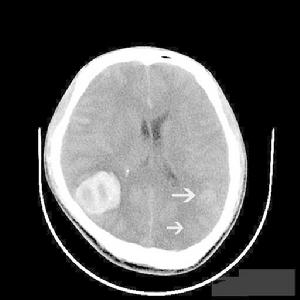

腦組織梗死液化(2)腦梗死:常起病突然,根據病情有穩定型和進展型之分,前者指病情穩定無進展,歷時24~72h又稱完全性腦卒中11%-13%患者起病隱匿無臨床症狀和體徵,僅影像學發現有缺血灶。

(4)腔隙性梗死:由小穿通動脈病損引起的腦深部微小梗死占腦梗死的12%~25%。梗死好發於基底節區以及丘腦、腦橋內囊和白質內,可隱匿起病、無症狀或表現為神經功能障礙意識狀態和高級皮質功能不受影響。